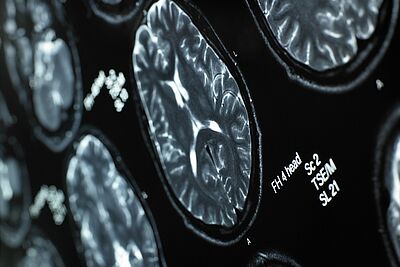

Les maladies du système nerveux sont des enjeux majeurs de santé publique. En France, plusieurs millions de personnes souffrent de maladies aiguës ou chroniques touchant le système nerveux.

Le service de neurologie du CHU de Rennes propose une prise en charge médicale adaptée pour de nombreuses pathologies neurologiques : épilepsie, sclérose en plaques, maladie de Parkinson, accidents vasculaires cérébraux, démence et maladie d'Alzheimer, maladies neuromusculaires.

Accident vasculaire cérébral, Epilepsie, Maladie d'Alzheimer et maladies apparentées, Maladie de Parkinson et mouvements anormaux, Myopathie, Pathologie neuromusculaire, Sclérose en plaques